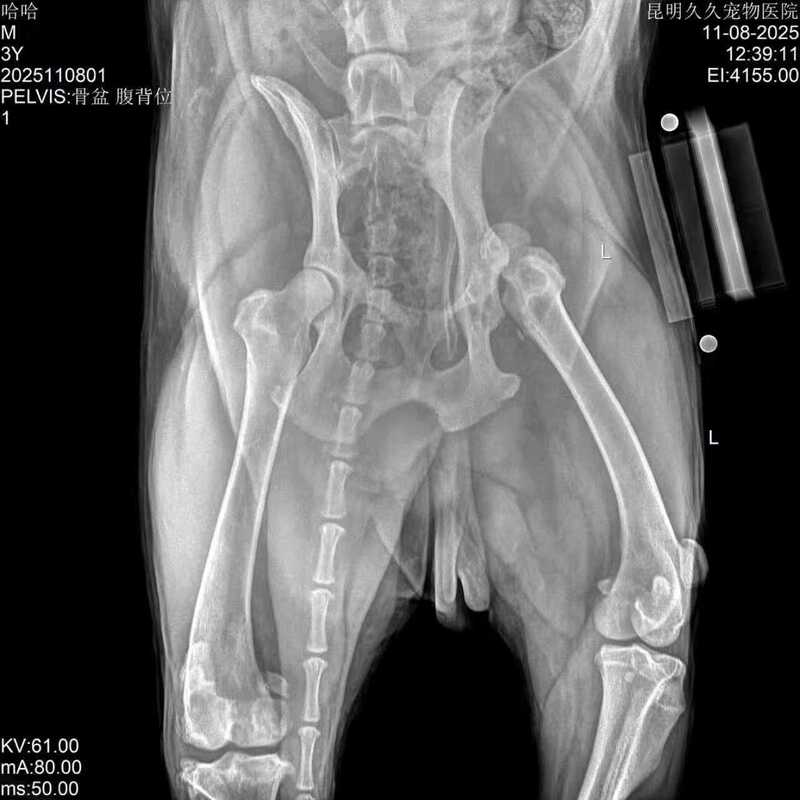

Golden Retriever, nickname: Haha, 3 years old, male, weighs 37 kilograms.

There has been a traumatic hip dislocation for 2 years. A hip replacement surgery has been decided. Before the operation, the precise surgical planning was carried out using the iBlueVet software. During the operation, the BlueSAO Bionic hip joint system was used for replacement. The implants included: 25mm bionic acetabular cup, 20mm PEEK femoral head, #7femoral stem, M+0 femoral neck, and 22 mm lateral bolt. The surgery was successfully completed. We hope for a speedy recovery.